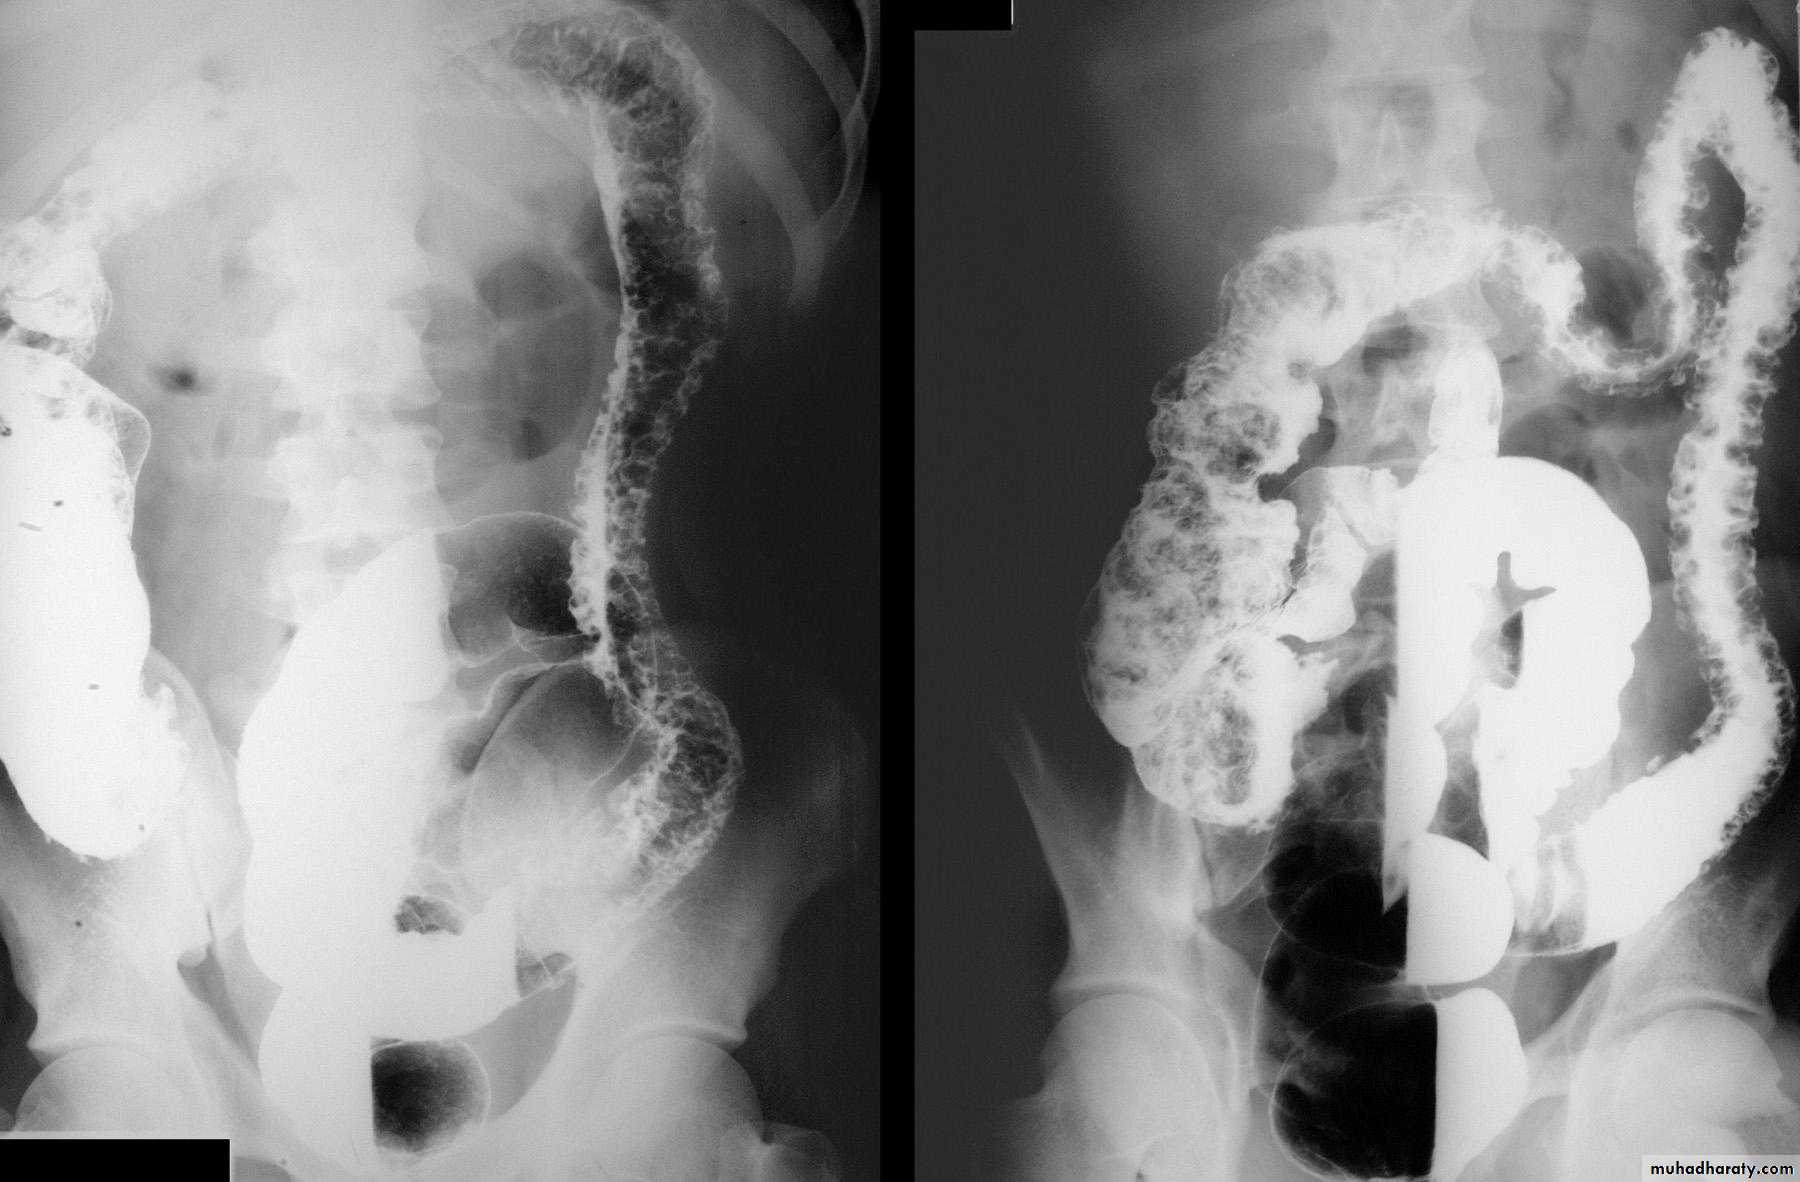

Ulcerative colitis

• Ulcerative colitis is a disease of large bowel characterized by mucosal ulceration and inflammation.

• The rectum is involved in virtually all cases with disease extending proximally in the colon.

• Distribution of disease is continuous with no ‘skip lesions’.

• Initial diagnosis of inflammatory bowel disease involving the colon is usually by endoscopy, either sigmoidoscopy or colonoscopy, including biopsy.

• Where colonoscopy is unavailable or contraindicated, barium enema may be performed.

Radiological signs:

• Widespread shallow ulcer is the cardinal sign. Ulcers may be deep in severe cases• Widening of the presacral space in early stage of disease due to peri-rectal edema

• Loss of the normal colonic haustra in the affected portions of the colon

• Narrowing and shorting of the colon giving the appearance of rigid tube (lead-pipe appearance).

• Pseudopolyps ( swollen mucosa between ulcers) seen as filling defects

• Strictures are rare and likely to be due to carcinoma in longstanding disease

• Abnormal dilated ileum due to reflux through an incompetent ileocecal valve

• Toxic megacolon is a serious complication diagnosed by plain abdominal film or native ct. Due to the risk of perforation, barium enema, colonoscopy and CT pneumocolon should be avoided.